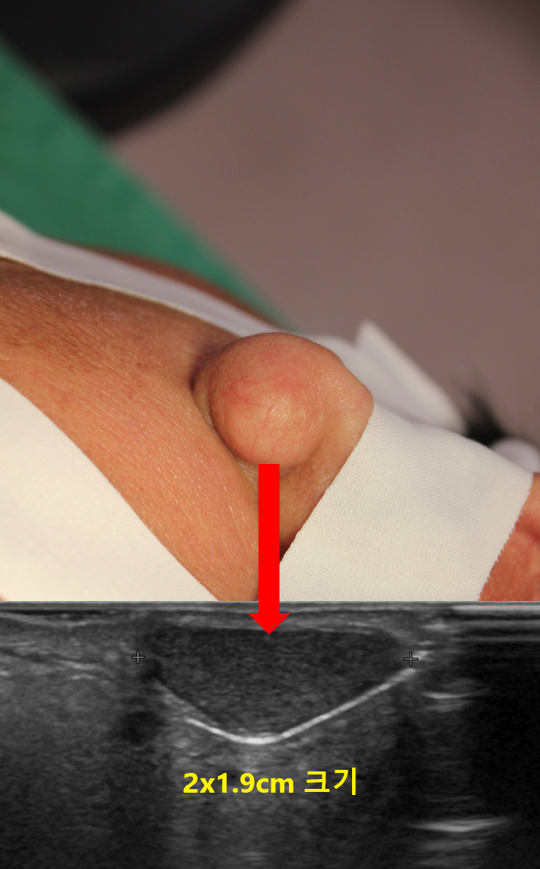

진찰상 밖에서 눈에 띌 정도로 왼쪽 귓볼에 약 2cm 크기의 단단한 혹이 만져졌습니다.

혹의 정확한 양상, 크기, 피부로 부터의 깊이 등을 확인하기 위해 초음파 검사를 시행하였습니다.

초음파상 가로x세로의 길이가 약 2x1.9cm 크기인 피지낭종으로 확인이 되었습니다.